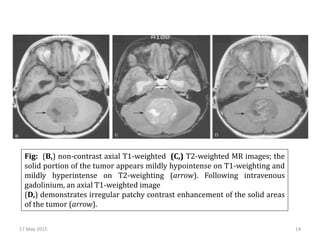

Fig: (B,) non-contrast axial T1-weighted (C,) T2-weighted MR images; the

solid portion of the tumor appears mildly hypointense on T1-weighting and

mildly hyperintense on T2-weighting (arrow). Following intravenous

gadolinium, an axial T1-weighted image

(D,) demonstrates irregular patchy contrast enhancement of the solid areas

of the tumor (arrow).